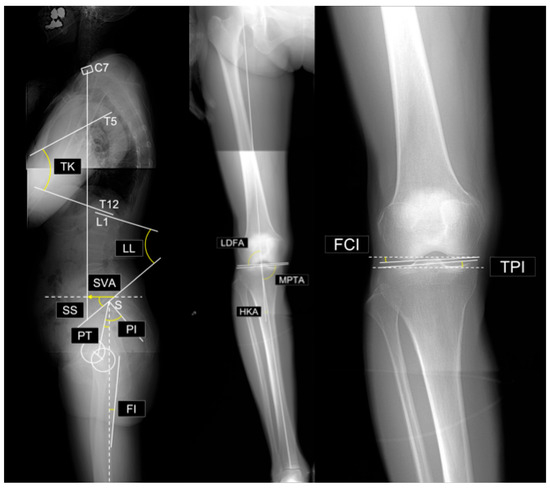

Body Mass Index and Spinopelvic Alignment as Predictors of Incident Knee Osteoarthritis: An 8-Year Longitudinal Study from the TOEI Cohort of Older Japanese Women

Background/Objectives: Knee osteoarthritis (KOA) is multifactorial, and longitudinal evidence isolating early predictors remains limited. We investigated predictors of incident KOA in community-dwelling older adult Japanese women. Methods: We analyzed 191 knees from 105 women aged ≥50 years (baseline Kellgren–Lawrence (KL) grade 0–1) and followed them for 8 years. Incident KOA was defined as KL ≥ 2 at the 8-year follow-up. Baseline measures included body mass index (BMI), physical function (one-leg stance, functional reach), Geriatric Locomotive Function Scale (GLFS-25), EuroQol 5-Dimension (EQ-5D) questionnaire, standing lateral whole-spine radiographs (sagittal spinopelvic parameters), and standing full-length anteroposterior (AP) lower-limb radiographs (coronal alignment parameters). Incident KOA was defined as KL ≥ 2 at follow-up. Group comparisons, multivariable logistic regression, and receiver operating characteristic analyses were conducted. Results: Incident KOA occurred in 58/191 knees (mean participant age 69.3 ± 6.1 years). Compared with non-incident knees, incident knees had higher BMI (23.8 vs. 21.1 kg/m2), higher GLFS-25, greater pelvic tilt and pelvic incidence minus lumbar lordosis (PI–LL) mismatch (11.5° vs. 5.3°), and lower EQ-5D, medial proximal tibial angle, and joint line obliquity. BMI was the strongest single predictor (area under the curve [AUC] 0.753). PI–LL mismatch showed limited standalone discrimination (AUC 0.596) but improved discrimination when combined with BMI (AUC 0.803). Conclusions: BMI was the primary predictor of incident KOA in this cohort. PI–LL mismatch, while not strongly discriminative alone, acted as a complementary marker consistent with sagittal-alignment-related mechanical stress. Results suggest that early screening and prevention should prioritize weight management, using spinopelvic parameters to refine risk stratification. Full article